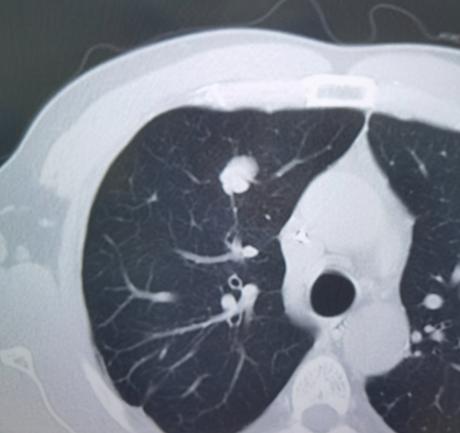

肿瘤最容易转移到肺?这项检查能帮你早发现、早干预!一位40岁左右的年轻男士,几年前确诊了肠癌,做完手术和化疗之后,恢复得一直不错,平时复查的各项指标也都正常。 直到一次常规的胸部CT复查,发现他的肺部出现了一个实性结节。一开始,这个结节大小没什么明显变化,当地医生就让他定期随访观察,但连续几次复查后,仔细对比影像片子才发现,这个结节其实一直在慢慢增大。 结合他之前有肠癌病史,我高度怀疑,这个肺部结节就是肠癌转移过来的。可能很多人不知道,肺部其实是全身肿瘤最容易转移的部位之一。 主要原因就是,全身的血液都要流经肺部进行氧气交换,而肺部布满了密密麻麻的血管,这就给肿瘤细胞的转移提供了便利条件,让它们容易在肺部“扎根”。 好在这个患者比较幸运,肺部只有这一个转移病灶,而且经过长时间的随访观察,没有发现其他部位有新的病灶。医院组织了多学科团队会诊评估后,为他做了肺部转移灶的局部切除手术。 手术很成功,术后复查也很理想,他不需要再做化疗或者其他后续治疗,相当于达到了临床治愈的效果。 其实,这样的病例在临床上并不少见。很多肿瘤患者做完原发灶手术之后,之所以能长期存活,关键就是定期做肺CT检查,早早发现了肺部的转移病灶,并且及时做了手术干预。 这些患者大多不用再承受化疗、放疗的痛苦,生存质量也能得到很好的保障。 这个病例也给所有肿瘤患者提了个醒:术后定期做肺CT检查,真的太重要了!肺部转移在早期的时候,几乎没有任何明显症状,既不咳嗽、也不胸闷,普通人根本察觉不到,但通过肺CT检查,就能清晰地发现早期的微小病灶,为治疗争取到最宝贵的时间。 尤其是那些本身就容易发生肺转移的肿瘤,比如肠癌、乳腺癌、肝癌等,肺部的定期筛查更是不能少,千万不能因为术后恢复得好,就掉以轻心,忽略了随访检查。[玫瑰][作揖]